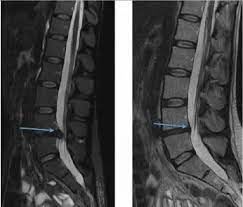

Rückenschmerzen, die Deutsche jahrelang auf Müdigkeit geschoben haben, sind zu einem schleichenden Urteil geworden, das kaum Heilungschancen lässt. Bandscheibenvorfälle zerstören das Leben schnell: Lähmung, Beinversagen, lebenslang der Rollstuhl – das ist die Realität für alle, die die Gefahr zu spät erkannt haben.